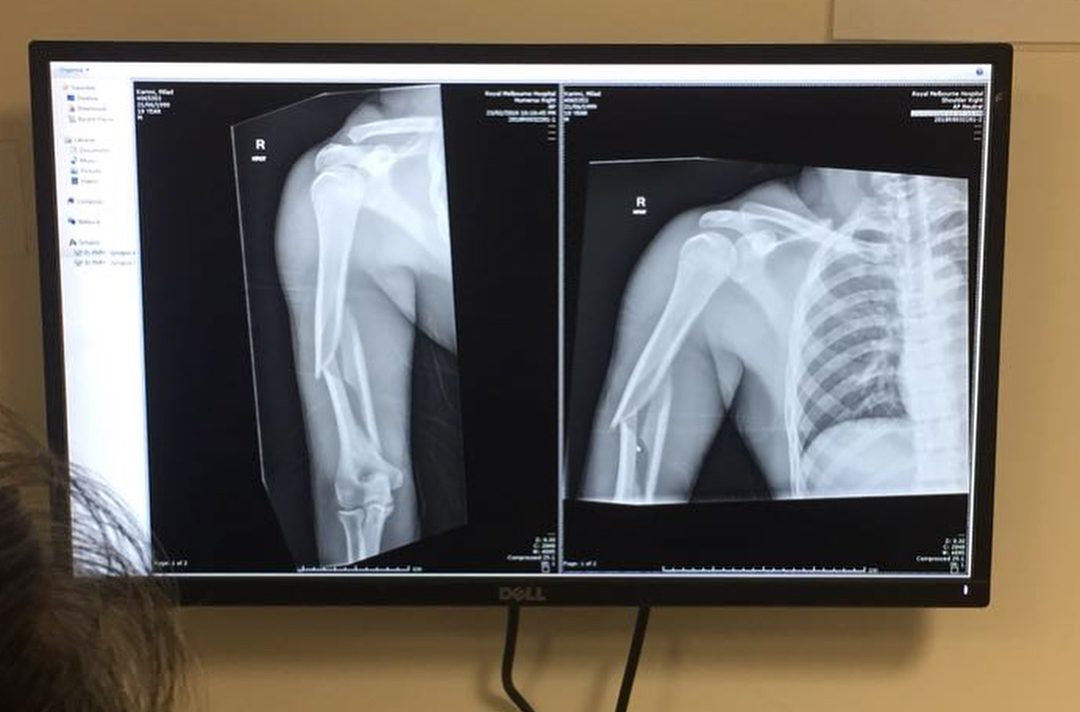

Напомним, что 19-летний на Кубке мира в Австралии во время выполнения упражнений на брусьях казахстанский гимнаст ударился о снаряд и получил серьезную травму — тройной перелом руки со смешением. Его тут же доставили в госпитале Royal Melbourne, где его прооперировали и вставили специальную пластину.